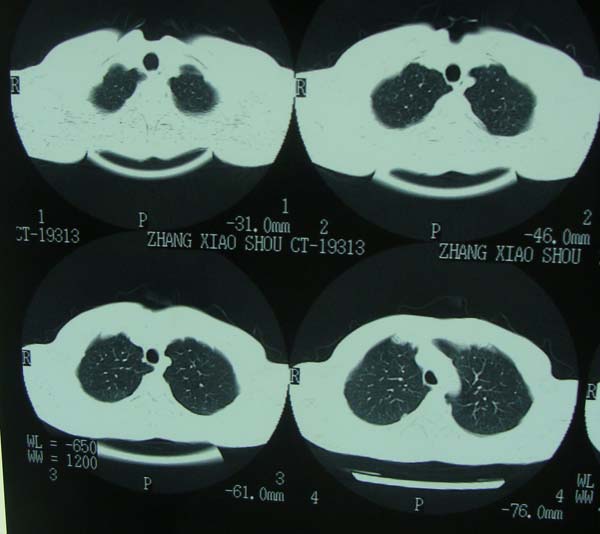

标题: CT15132:男,26岁。建筑混凝土工人。发热。咳。 [打印本页]

标题: CT15132:男,26岁。建筑混凝土工人。发热。咳。

右肺继发型肺结核,右侧胸腔积液、胸膜肥厚粘连。

右肺继发型肺结核,右侧胸腔积液。

年轻男性,右肺多形性病灶伴右侧胸腔积液,考虑结核

右肺继发型肺结核,右侧少量胸腔积液、胸膜肥厚。